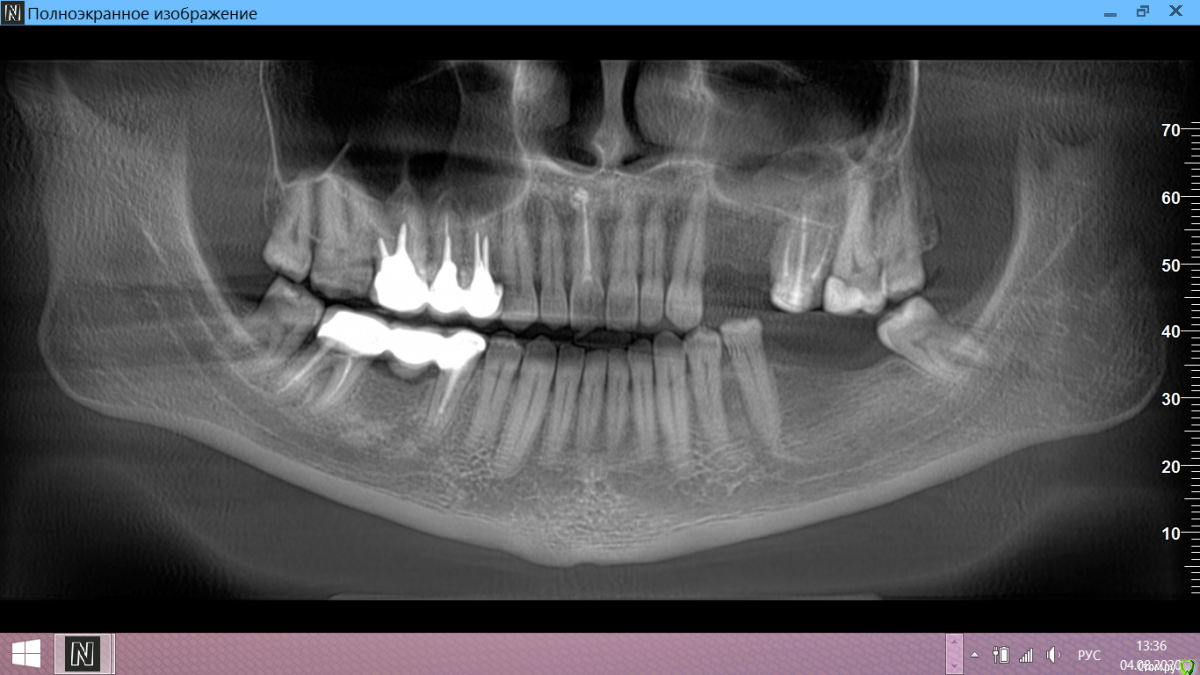

Олька11 Опубликовано 4 августа, 2020 Поделиться Опубликовано 4 августа, 2020 Здравствуйте!Женщина, 42 года, хронических заболеваний нет. Отсутствуют два зуба вверху и два внизу, зубов нет более 5 лет. Врач предлагает поставить 4 импланта, говорит наращивание кости не требуется.Оцените, пожалуйста, действительно можно сразу ставить импланты. Ссылка на комментарий

red_butler Опубликовано 4 августа, 2020 Поделиться Опубликовано 4 августа, 2020 По этому снимку можно судить только о высоте, с ней проблем нет Ссылка на комментарий

колесников Опубликовано 5 августа, 2020 Поделиться Опубликовано 5 августа, 2020 На верху два импланта не проходят. Один имплант и коронка с консолью от шестерки (или оттимпланта). Внизу вероятнее всего узкий гребень челюсти в проекции первого импланта,потребуется как минимум 3д снимок для уточнения и пластика десны. Ссылка на комментарий